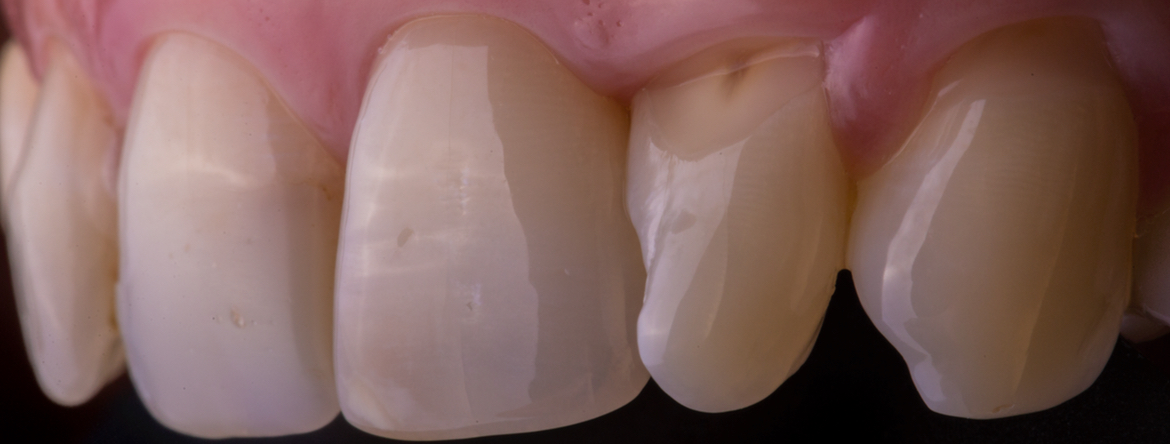

Todos os parâmetros para obter a fotografia perfeita Setups Fotográficos Intra-orais em MD:

Todas as dicas e truques para nunca perder um caso Sessão Prática de Fotografia Clínica Intra-oral Organização e Classificação de Ficheiros Poupe tempo na pesquisa dos seus casos e organização de apresentações Darkroom Digital em MD Utilização de software para edição de imagem.

Dicas para obtenção de fotografias para Melhor transmissão de todas as informações:

– Matiz, Croma, Valor, Translucidez, Opalescência, Textura.